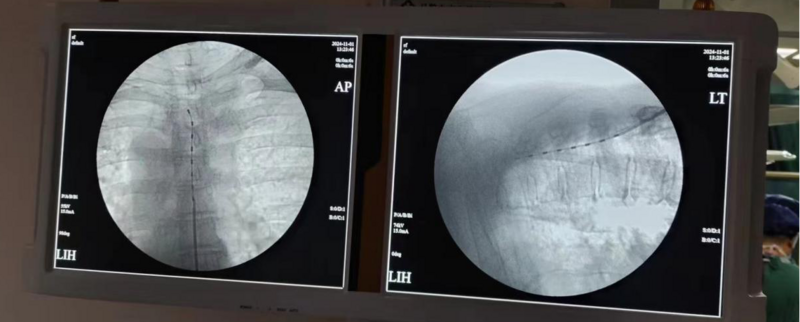

以我科住院治療的潘女士為例,入院時右上肢疼痛呈持續(xù)性的火燒樣、針刺樣和酸脹性疼痛,伴右手大魚際肌萎縮,肌力下降2月余。口服鎮(zhèn)痛藥物效果很差,生活和睡眠質(zhì)量嚴重受擾。經(jīng)過醫(yī)護團隊的精心治療,在G型臂X光機和超聲引導下,將射頻穿刺針置入相應神經(jīng)節(jié),予以脈沖射頻微創(chuàng)手術(shù)治療,術(shù)后第二天起潘女士的疼痛即大幅減輕,生活質(zhì)量明顯改善。

脊髓神經(jīng)電刺激鎮(zhèn)痛術(shù):將刺激電極置入硬膜外腔(上圖),通過電流刺激脊髓后柱傳導束,阻斷疼痛信號以達到治療疼痛的目的。